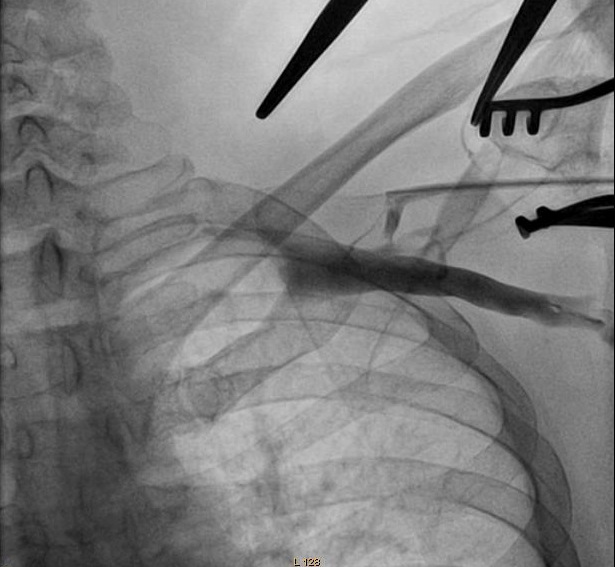

Puncture with venogram